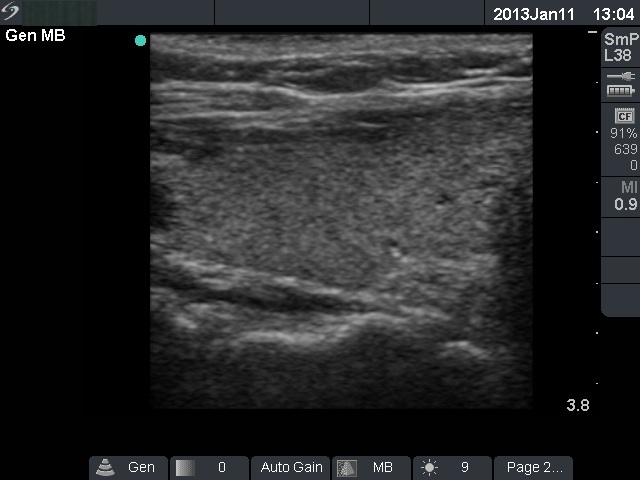

Follow-up examination 19 months later (3rd row of images):

Clinical presentation: the patient had no complaints.

Palpation: no abnormality.

Functional state: subclinical hyperthyroidism (TSH 1.96 mIU/L, FT4 13.6 pM/L, sedimentation rate 2 mm/H, CRP 1.38 mg/L).

Ultrasonography: the thyroid became echonormal.